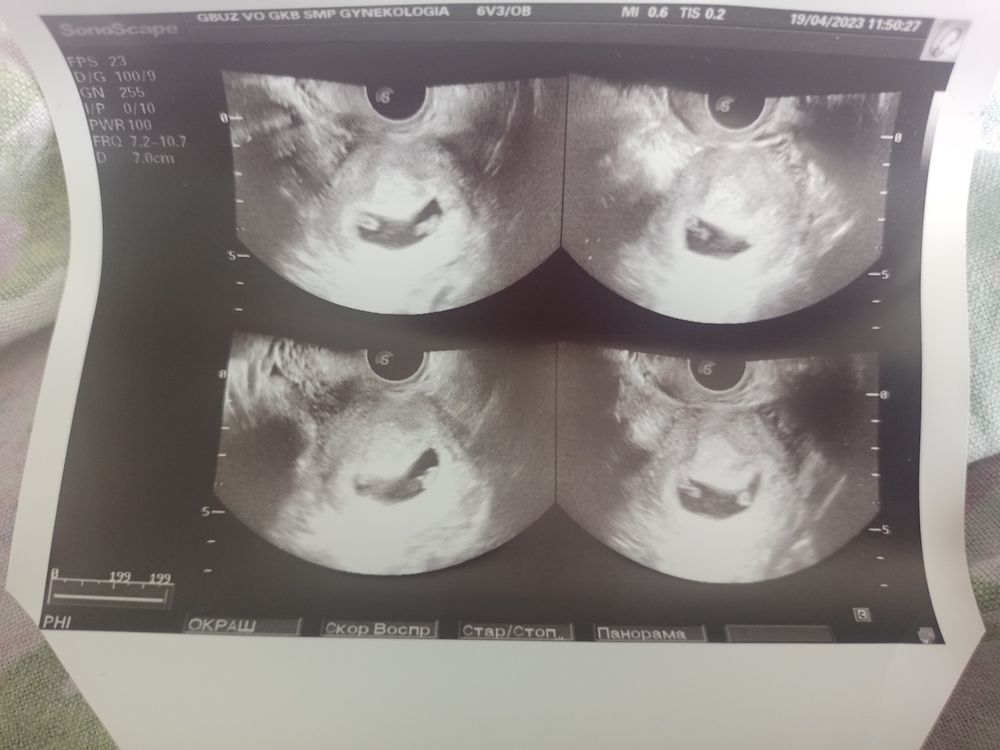

УЗИ близнецы

У вас одно плодное яйцо и два желточный мешочек на узи у вас близнецы

На вашем снимке похоже на моно ди . Одно пя и два жм( плода?)

06.09.2024